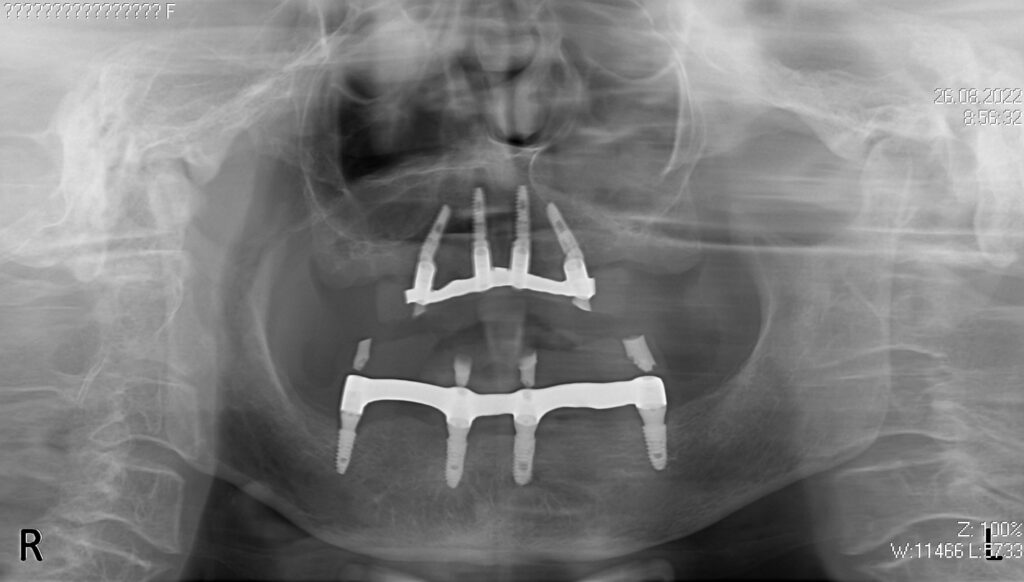

На верхней и нижней челюстях были удалены зубы и проведена комплексная имплантация по системе All-on-4, установлены 8 имплантатов Osstem.

Спустя 7 дней на обеих челюстях зафиксированы металлоакриловые протез из 12 зубов.